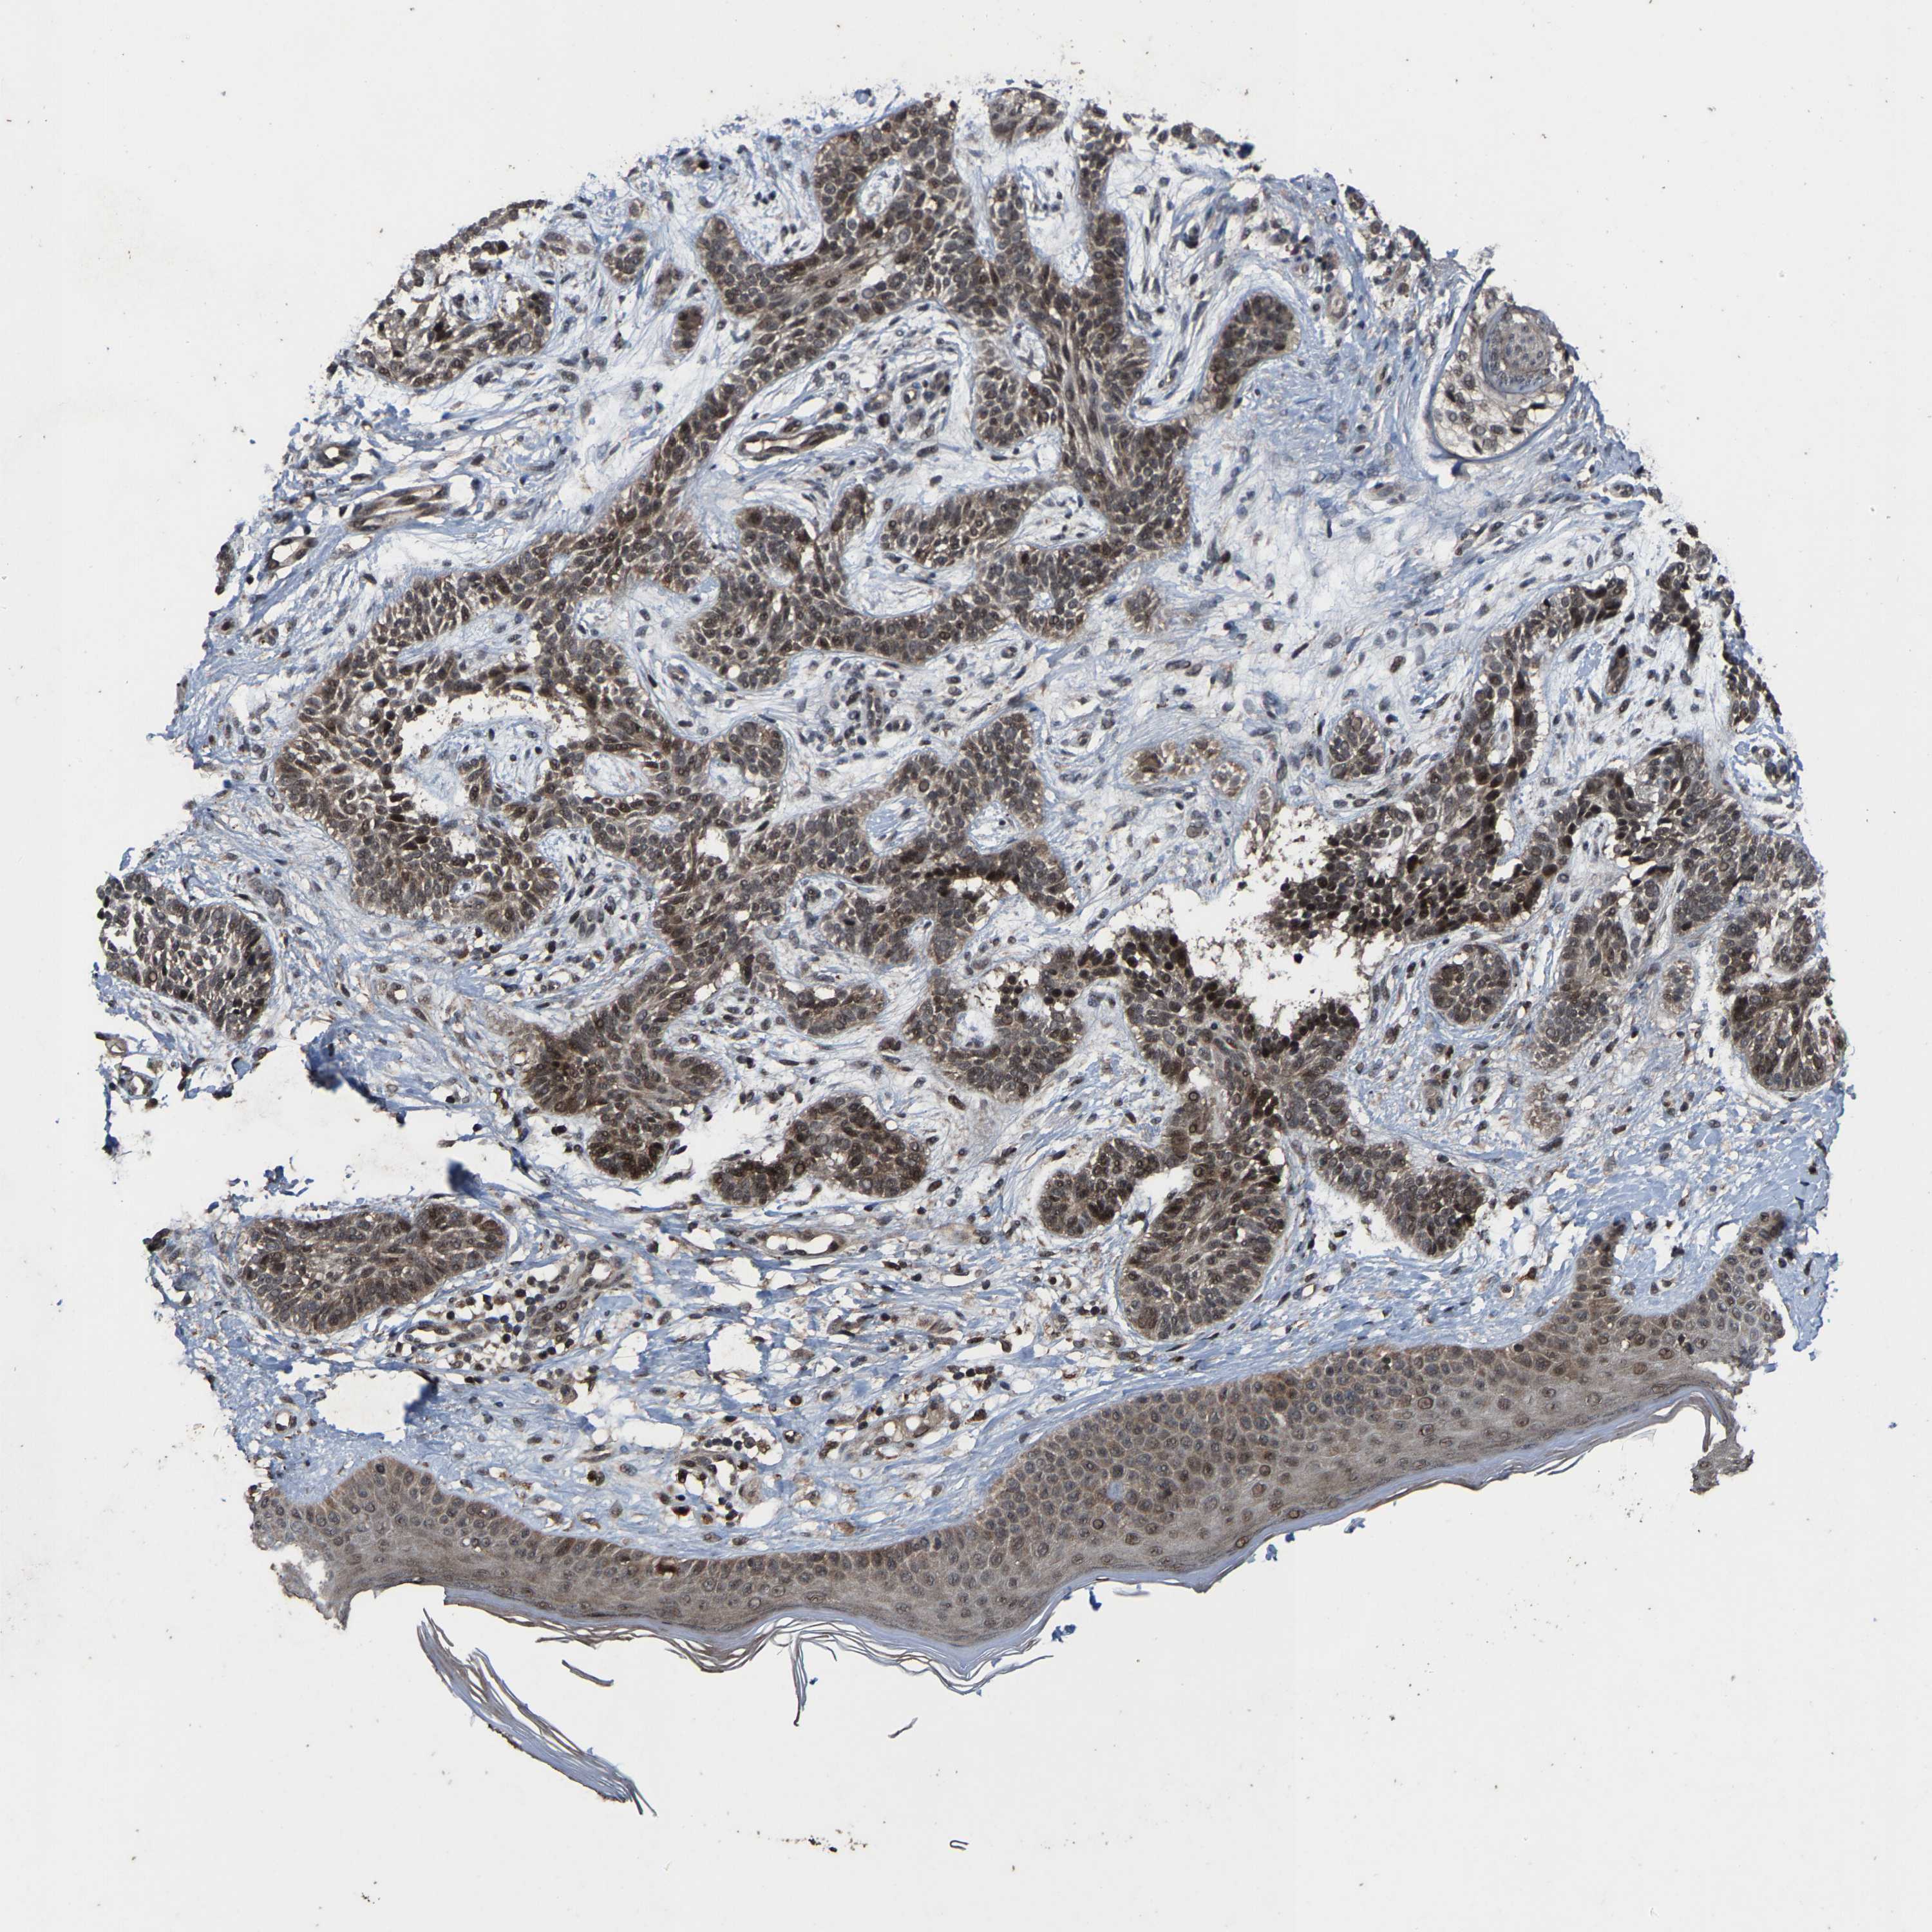

Basal cell and squamous cell cancer

SKIN CANCER - Protein expressioni

A mouse-over function shows sample information and annotation data. Click on an image to view it in a full screen mode. Samples can be filtered based on level of antibody staining by selecting one or several of the following categories: high, medium, low and not detected. The assay and annotation is described here.

Antibody stainingi

Antibody staining in the annotated cell types in the current human tissue is reported as not detected, low, medium, or high, based on conventional immunohistochemistry profiling in selected tissues. This score is based on the combination of the staining intensity and fraction of stained cells.

Each image is clickable and will lead to virtual microscopy that enables deeper exploration of all samples and also displays staining intensity scores, fraction scores and subcellular localization as well as patient and tissue information for each sample.

Antibody HPA020960

Antibody HPA020965

Staining

High

Medium

Low

Not detected

Intensity

Strong

Moderate

Weak

Negative

Quantity

>75%

75%-25%

<25%

None

Location

Nuclear

Cytoplasmic/membranous

Cytoplasmic/membranous,nuclear

Basal cell carcinoma

Squamous cell carcinoma, NOS

Squamous cell carcinoma, metastatic, NOS